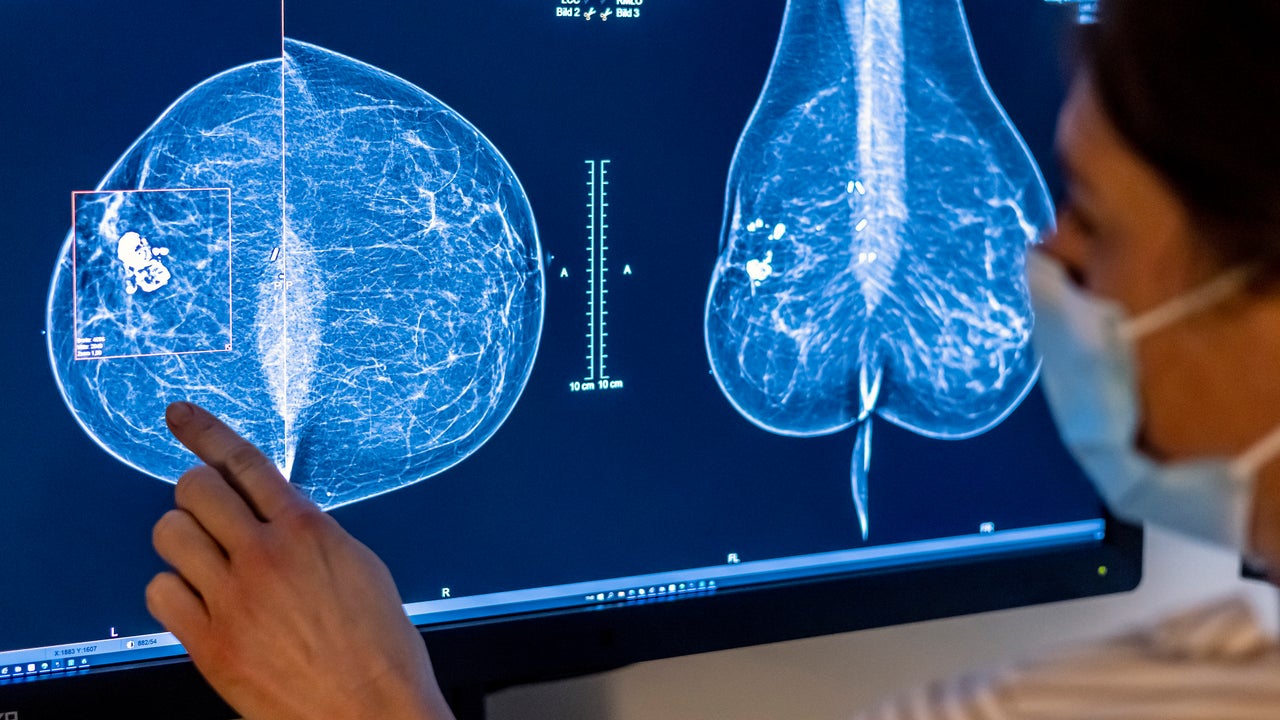

Medical personnel use a mammogram to examine a woman's breast for breast cancer. Photo: Hannibal Hanschke/dpa (Photo by Michael Hanschke/picture alliance via Getty Images)

About half of women over age 40 have dense breasts, with less fatty tissue and more connective and glandular tissue. That tissue appears white on X-rays, the same color as growths in the breast, making mammograms harder to read. Dense breast tissue is one of the factors that can increase a woman’s chances of developing cancer.

Under the new rules, women with dense breasts will receive a written memo alerting them that their status "makes it harder to find breast cancer." Those patients will also be directed to speak with their doctor about their results.